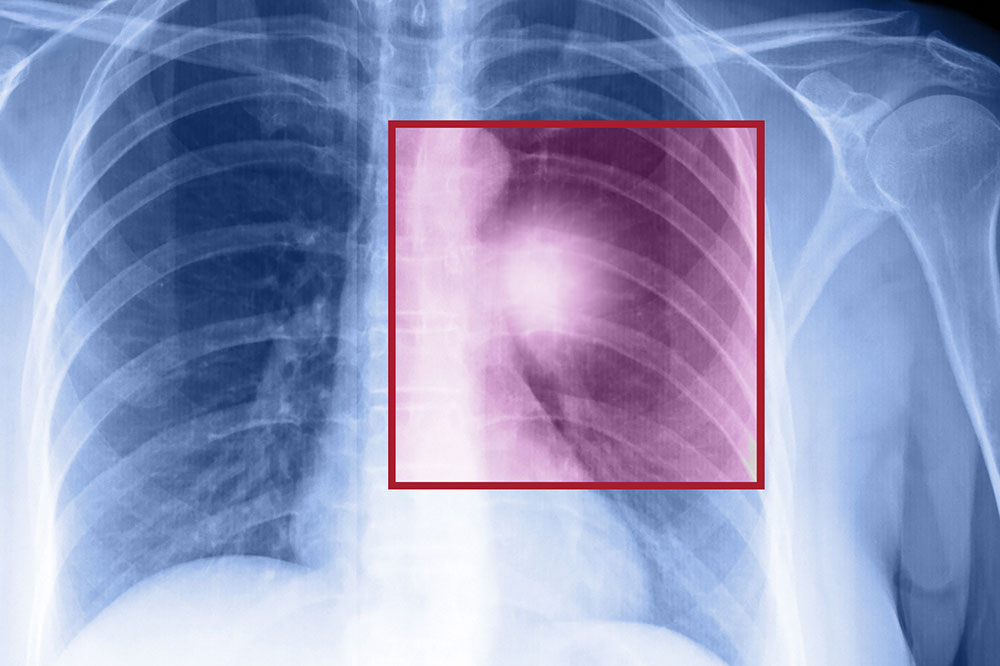

When the cells in the lungs begin to abnormally multiply and grow, it results in cancer. Lung cancer is one of the leading causes of death in the world. And the risk of suffering from this life-threatening disease is even higher when one is a smoker. Herein, we discuss the various factors that come into play when it comes to lung cancer.

Types of lung cancer

There are two kinds of lung cancer:

• Non-small cell lung cancer

This is a catchall term that includes many varieties of this disease, like large cell carcinoma, squamous cell carcinoma, and adenocarcinoma.

• Small cell lung cancer

This happens mainly to people who are heavy smokers, and it’s rarer than non-small cell lung cancer.